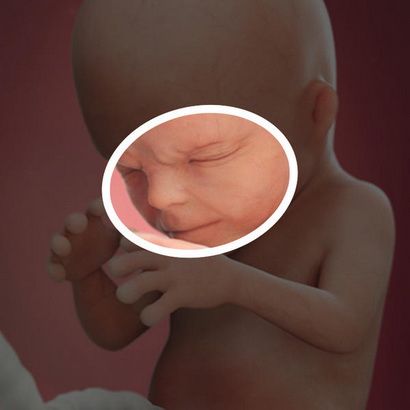

Як розвивається малюк? До цього терміну зріст і вагу дитини порівнянні з плодом авокадо і становлять 10,8 – 12 см і 80 – 115 р. При проходженні процедури УЗД на даному терміні, лікар виробляє виміри довжини і обхвату окремих частин тіла. Голова в 14 тижнів має окружність в 11 – 13 див. Пуповина, яка забезпечує харчування малюка має діаметр дорівнює 2 см, а її довжина становить близько 50 див.

Внутрішньоутробний розвиток плода: опис та фото, на цьому терміні дозволяють точно визначити стать дитини. Інтенсивний розвиток органів і систем триває. До особливостям періоду відносяться такі зміни:

Незважаючи на те, що очі на даному терміні виглядають ще дуже опуклими, вони вже розташовані на своєму місці, а обличчя дитини вже повністю відповідає людському. Малюк вже вміє не тільки піднімати і опускати голову, але і повертати її.